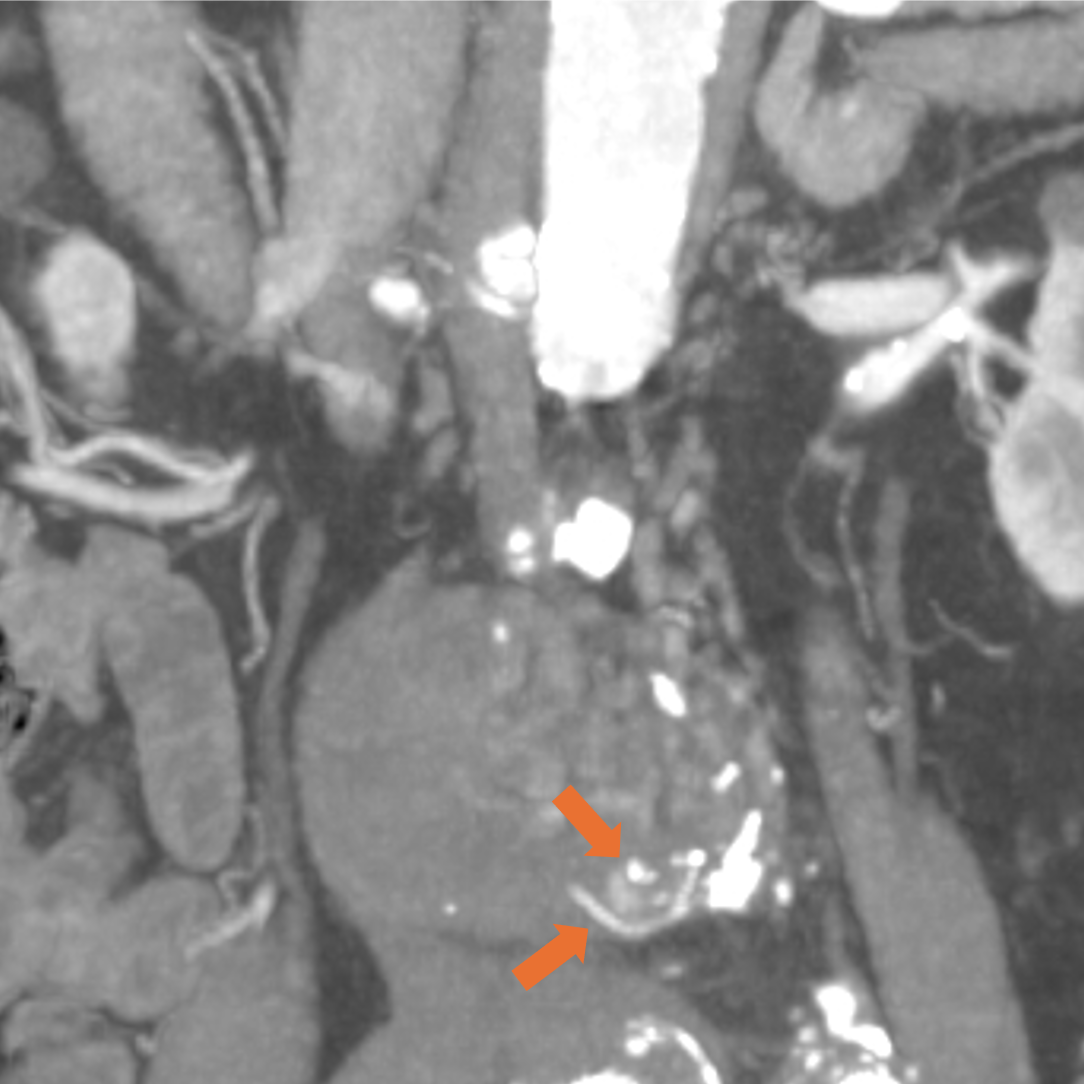

症例は80代男性。7年前に腹部大動脈瘤と右総腸骨動脈瘤に対しEVAR、2年前に腹部大動脈瘤のエンドリークに対し、下腸間膜動脈からコイル塞栓を行っている。動脈瘤が拡大傾向であったため、超音波検査が行われ、エンドリークが疑われた。評価と治療方針決定が必要と判断されたが、腎機能障害があったため入院での造影CTが計画された。

当該疾患の診断における造影CTの役割

CT技術や撮像プロトコル設定について

当院で使用されているCTは256列でのDual energy CTの撮影が可能なGEヘルスケア社のRevolution CTである。従来のSingle energy CTは1種類の管電圧を使用し、1種類のX線エネルギーを使用した撮像を行うが、本機種では高管電圧と低管電圧の2種類の異なる管電圧からそれぞれのX線エネルギーを使用した撮像が可能である。それにより、高画質かつ高コントラストの水密度画像とヨード密度画像が作成可能で、Deep learningを用いて解析を行うことでノイズの低減されたCT画像を再構成できる。本症例のようにTypeⅡエンドリークでは微小な血管が関与している場合があり、その検出と詳細な血管走行の確認において高コントラストかつ高画質の画像が求められ、Dual energy CTは有用である。